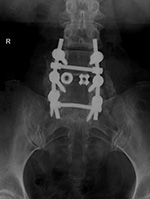

Posterior spinal fusion apparatus |

Shown are pedicle screws and rods on each side, two crosslinks (at L4 and S1), and intervertebral disk spacers at L4-5. |